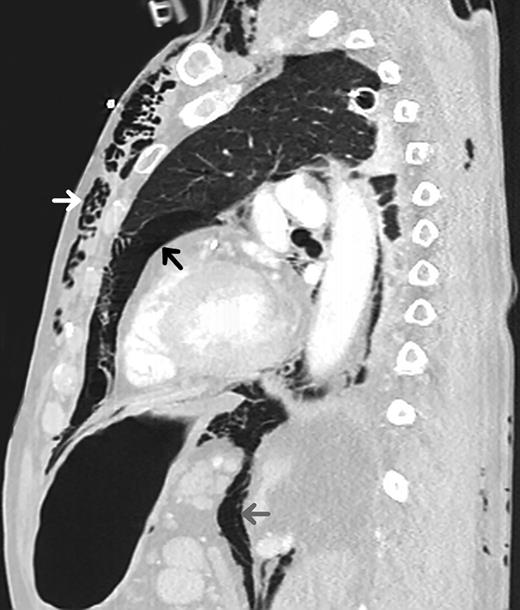

An 82-year-old male with past medical history of diabetes mellitus and alcohol abuse arrived by ambulance after being found unresponsive at the bottom of a flight of stairs with a scalp laceration. While en route to the hospital, two unsuccessful intubation attempts were made for a Glasgow coma scale (GCS) of 8. Upon arrival in the emergency department (ED), his GCS was determined to be 3 and was intubated with use of the Glidescope. Physical examination revealed decreased breath sounds on the left and crepitus over the left chest wall, suggestive of subcutaneous emphysema, and an immediate tube thoracostomy was performed prior to chest X-ray (CXR) to reduce the suspected pneumothorax. CXR post chest tube placement demonstrated large amounts of subcutaneous emphysema (Fig. 1 ), which was also visible on computed tomography (CT) scan along with evidence of pneumomediastinum and pneumoperitoneum (Fig. 2), with pneumoretroperitoneum and pneumoperitoneum present on abdominal CT scan (Fig. 3). As a result of the fall, he also sustained a fracture of the right frontal bone, fractures of the C2 and C3 vertebrae, and mild subarachnoid and subdural hemorrhage without shift. There were no intra-abdominal injuries found. He was admitted to the surgical intensive care unit (SICU) and maintained on mechanical ventilation, remaining hypotensive, hypothermic and mildly tachypneic, becoming increasingly unstable over the next 8 h. Due to the known pneumomediastinum, pneumoperitoneum and worsening instability, he was taken to the operating room for suspected viscus perforation and peritonitis. An exploratory laparotomy was performed, which revealed air within the lesser sac, but no evidence of bleeding or perforation. When closing the operative site, crepitus was also noted over the right chest wall, and a chest tube was placed into the right pleural space.

Chest CT scan obtained shortly after patient's arrival displaying evidence of subcutaneous emphysema (white arrow), pneumomediastinum (black arrow) and air tracking down resulting in pneumoperitoneum (gray arrow).